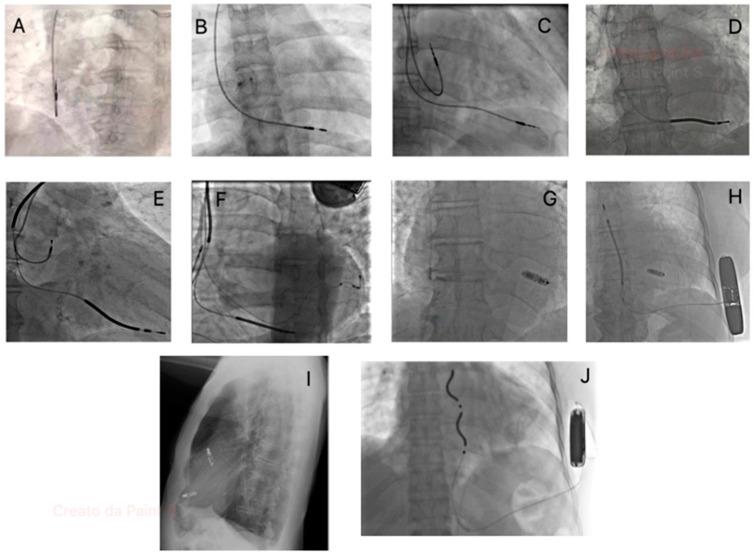

The widespread use of Cardiac Implantable Electronic Devices (CIEDs) has transformed the management of cardiac arrhythmias, improving survival and quality of life for millions. However, this progress has introduced a range of device-related complications, which can significantly impact patient outcomes. This review examines "new diseases" linked to CIEDs, categorizing them into physical (e.g., infections, venous obstruction, lead failure, and device recalls) and functional complications (e.g., arrhythmias, pacemaker syndrome, and left ventricular dysfunction). Prevention and management strategies are emphasized. Emerging technologies, such as leadless devices, quadripolar leads, and remote monitoring systems, hold promise in reducing risks and enhancing patient care. Future directions include integrating artificial intelligence for real-time monitoring, improving device durability, and exploring novel materials to minimize infections and mechanical failures. Understanding CIED-related complications is essential for healthcare providers to balance the benefits and risks of these life-saving technologies.

心脏植入式电子设备(CIEDs)的广泛应用改变了心律失常的管理方式,提高了数百万人的生存率和生活质量。然而,这一进展也带来了一系列与设备相关的并发症,这些并发症会对患者的治疗结果产生重大影响。本综述探讨了与CIEDs相关的“新疾病”,将其分为物理性并发症(如感染、静脉阻塞、导线故障和设备召回)和功能性并发症(如心律失常、起搏器综合征和左心室功能障碍)。文中强调了预防和管理策略。诸如无导线设备、四极导线和远程监测系统等新兴技术有望降低风险并改善患者护理。未来的发展方向包括整合人工智能进行实时监测、提高设备耐用性以及探索新型材料以尽量减少感染和机械故障。了解与CIEDs相关的并发症对于医疗保健提供者平衡这些救生技术的益处和风险至关重要。